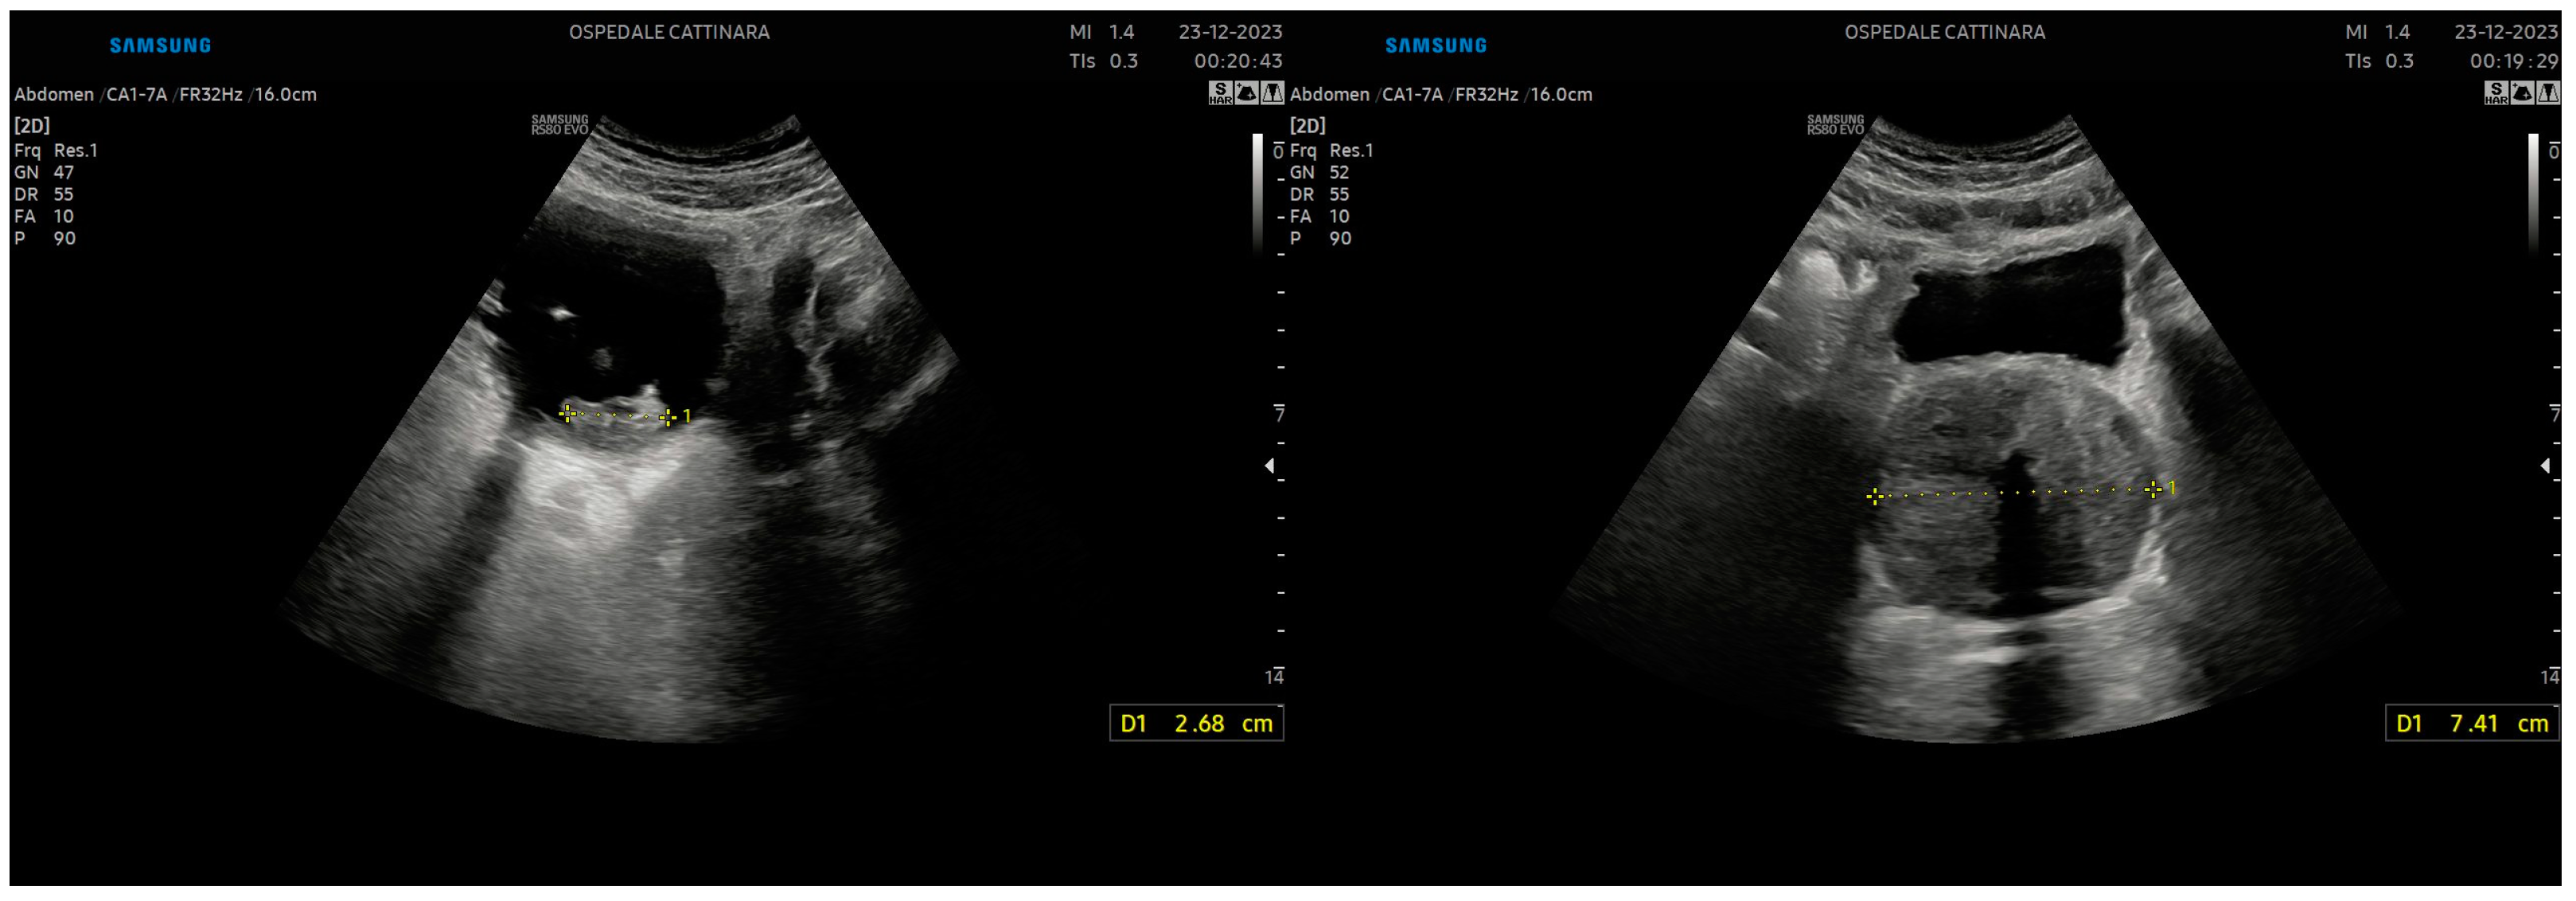

3.3. Renal Colic

3.4. Ureteral Stone